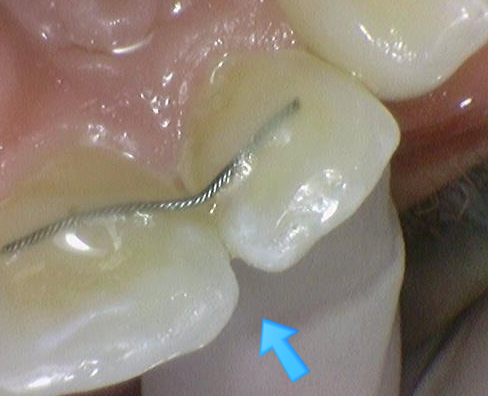

↑ 두 치아중 한치아를 먼저 치료한 사진

↑ 둘다 레진 충치치료 완료한 사진